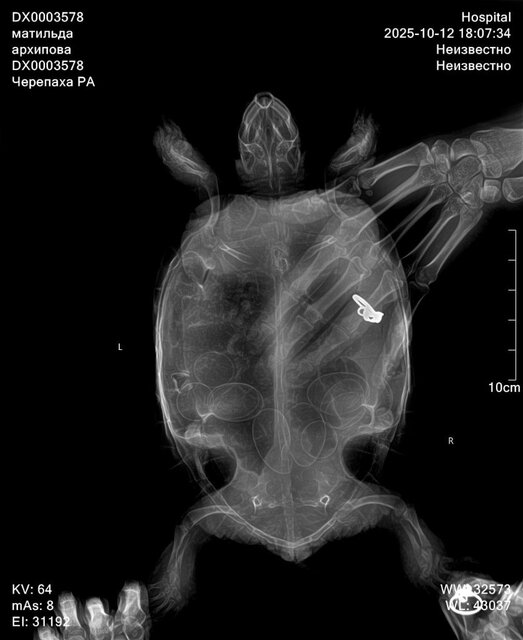

Доброго времени. В результате лечения отёки с лап ушли, с первой "заболевшей" лапы совсем, со второй практически сошли на нет. Доктор на повторном приёме осмотрела, сделала повторный снимок. (На рентгене 11 яиц)  посоветовала дать время на полное восстановление и не применять окситоцин ещё неделю. (Так и поступили) Также она отметила улучшение состояния Матильды: активное поведение при осмотре, во время снимка, её аппетит. На самом деле черепаха вела себя подвижно в кабинете и по дороге домой. Сейчас по прошествии почти 7 дней по прежнему преимущественно спит на одном месте, не активничает в воде (в воде и на поверхности держится хорошо) забирается на остров, сушу и спит. Остаются сомнения и беспокойство по поводу её поведения. Каковы признаки того что животное собирается впасть в спячку? Нет ли таких у неё? Если нет полного восстановления её состояния за две недели -нужно бить тревогу? Или я тороплю события?

Здраствуйте, сегодня обратилась в другую клинику, прогноз не благоприятный, есть признаки почечной недостаточность, есть переизбыток бактерий в кале, есть признаки стоматита в полости рта. Все это очень и очень плохо. Сделали рентген по направлению, к сожалению описание рентгена рентгенологи сделать не могут, без дополнительной платы. Но завтра я уже записана со снимками на повторный приём. Моя огромная ошибка что ограничилась визитами к одному доктору, и потеряла очень много времени. Тк изначально состояние более стабильное хотябы визуально. Завтра получим назначения от главного врача специалиста по экзотам. Покажу им новые снимки. По фото вроде насчитала тоже количество яиц. Но они значительно сместились, вероятно из-за не к месту сделанного окситоцина